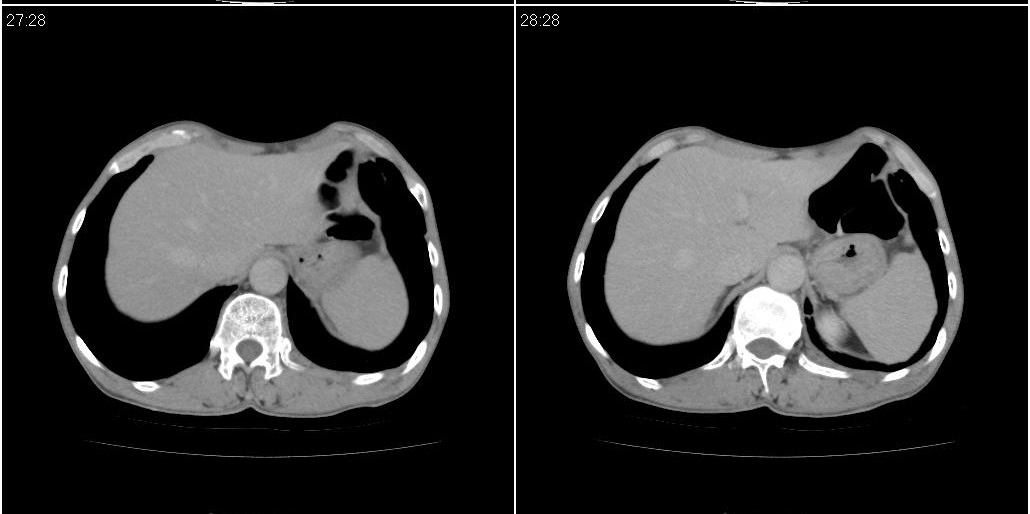

1)右肺中叶慢性炎症并支气管扩张,节段性肺不张。2)两肺下叶支气管扩张。

1)右肺中叶慢性炎症并支气管扩张,节段性肺不张。2)左肺下叶支气管扩张